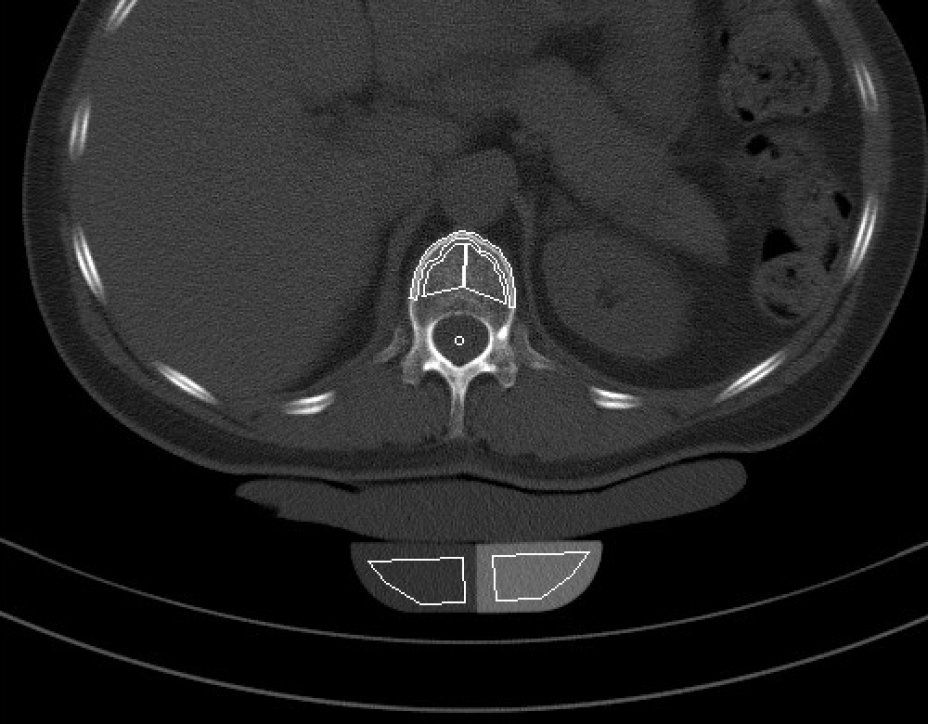

Die Knochendichtemessung mittels Computertomographie (Q.CT) ist eine der genausten Methoden zur Bestimmung der Knochendichte und gilt als Goldstandard. Sie ist sowohl für die Diagnosestellung als auch zur Verlaufskontrolle geeignet. Zur Bestimmung der BMD (engl.: Bone Mineral Density) werden bei der quantitativen Computertomographie ca. 3 bis 4 Scans von der Lendenwirbelsäule angefertigt. Aus der Knochendichte dieser Wirbelkörper wird der Mittelwert ermittelt. Dieser wird dann mit der Knochendichte eines gleichaltrigen Knochengesunden verglichen und in Relation dazu gesetzt. Je nach der Dichte des Knochens wird die Osteoporose dann in mehrere Stadien eingeteilt. Da die Knochendichtemessung (Q.CT) keine Kassenleistung ist, bieten wir die Untersuchung als

IGEL - Leistung an.

Q-CT gestützte Knochendichtemessung

Osteoporose - Auswertungszusammenfassung